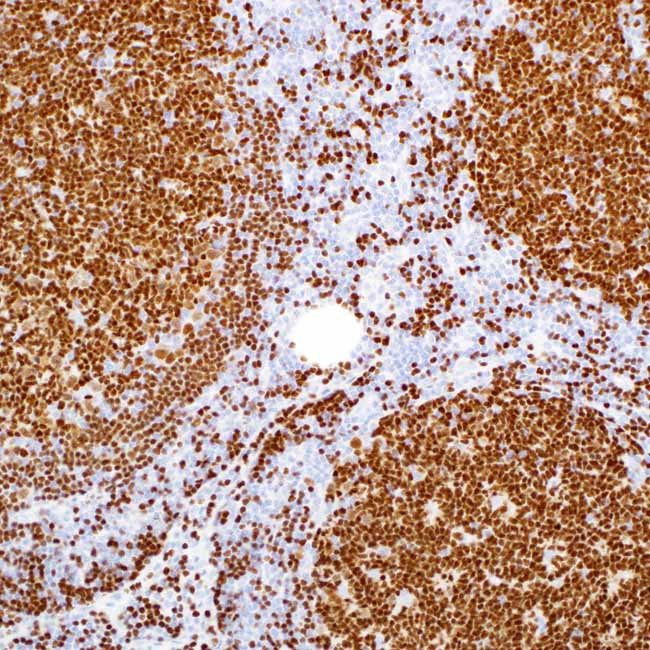

PAX-5 is responsible for producing a protein known as B-cell-specific activator protein (BSAP), which serves as a marker for B-cells, including B-lymphoblastic neoplasms and their development stages. This marker is present in nearly all instances of both mature and precursor B-cell non-Hodgkin lymphomas and leukemias. Around 97% of classic Hodgkin lymphoma cases show PAX-5 expression in Reed-Sternberg cells. PAX-5 is absent in multiple myeloma and solitary plasmacytoma, which aids in their differentiation. Diffuse large B-cell lymphomas do show PAX-5, except for those that have reached the final B-cell differentiation stage. T-cell neoplasms do not react with anti-PAX-5 staining. There is a strong link between PAX-5 and CD20 expression.